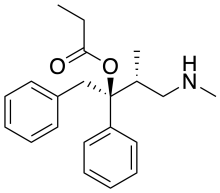

- Dextropropoxyphene (propoxyphene)

Structures

| Phenalkoxams | ||||

|